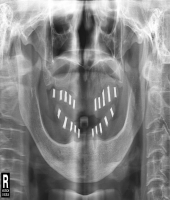

| ● 진료과목 : [임플란트] 틀니 사용중, 임플란트로 교체하기

| ● 내용 : 하악틀니 사용 중 불편감으로 임플란트로 교체한 예 |